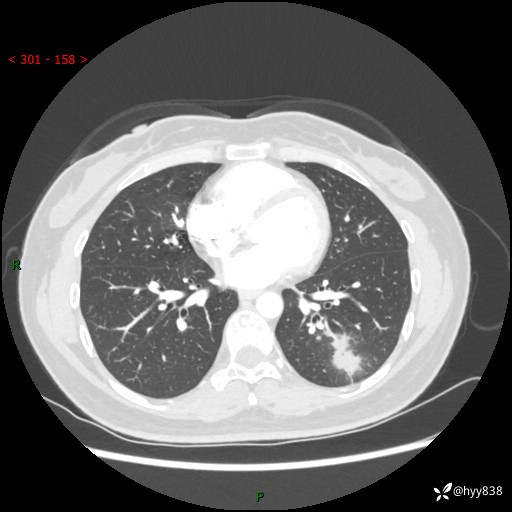

【患者信息】:36岁/女

【主诉】:左侧下胸部阵发性疼痛2周,乏力1周

【现病史及既往史】:患者自诉2周前饮酒后出现左侧下胸部阵发性疼痛,不随呼吸改变,无咳嗽咳痰、头晕头痛、咳血、呼吸困难等不适,于当地第一人民医院查胸部CT提示肺部感染,随后前往我院门诊给予抗感染(左氧氟沙星)治疗1周,自诉胸痛较前好转,感乏力、头晕,偶尔干咳,无咳痰,无发热、畏寒、胸闷、咯血、四肢酸痛、腹泻、腹痛等不适,门诊复查胸部CT提示:左肺下叶感染,病灶较前增加增大,遂以“肺部感染”收入我科。 起病以来,患者精神、饮食、睡眠可,大小便正常,体力体重无明显变化。

【检查】:胸部CT增强(外院平扫)